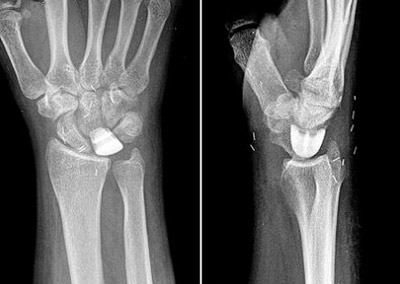

- در مرحله دوم: در رادیوگرافی ساده رنگ استخوان لونیت سفیدتر دیده می شود. درد و محدودیت حرکت بیمار در این مرحله شدیدتر می شود.

در این بیماری بهصورت شایعی مشاهده شده است استخوان زند زبرین نسبت به استخوان مجاور طول بیشتری داشته و بلندتر است. از آنجا که استخوان هلالی در مچ دست در مجاورت استخوان زند زبرین قرار داشته و با آن مفصل میشود.

این فرضیه مطرح میباشد که طول بیشتر استخوان زند زبرین، استخوان هلالی را تحت فشار قرار داده و جریان خون آن را در معرض خطر قرار میدهد لذا عمل جراحی که به طور معمول برای این عارضه توصیف شده است بر این نظریه استوار است.

در این روش طی عمل جراحی استخوان زند زبرین را به اندازه چند میلیمتر کوتاه میکنند تا در مچ دست فشار از روی استخوان هلالی برداشته شود. این عمل جراحی در نیمه تحتانی ساعد انجام شود، استخوان زند زبرین بریده شده و به اندازه چند میلیمتر کوتاه میشود و سپس با پیچ و پلاک فیکس میگردد. اندام فوقانی مبتلا پس از عمل جراحی به مدت دو تا سه ماه گچگیری میشود.